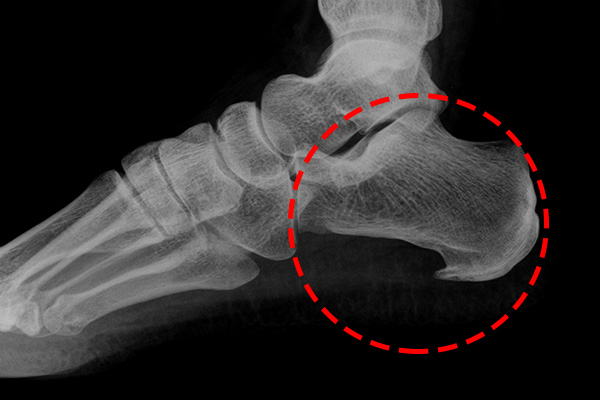

족저근막은 발바닥의 두꺼운 섬유질 막으로 발의 아치를 형성하고 걸을 때 발을 강력하게 지지해줍니다. 걸으면서 발뒤꿈치를 올리면 발뒤꿈치의 족저근막 부착 부위에 높은 장력이 가해집니다.

특히 달리기와 같은 활동 중에는 더 높은 장력이 가해져서 족저근막 부착 손상의 위험이 증가하게 됩니다. 족저근막염은 가벼운 부상이나 과도한 사용으로 인한 염증으로 발뒤꿈치와 발바닥에 통증을 일으키는 질환입니다. 아침에 일어나서 방바닥에 발을 딛는 순간 통증으로 깜짝 놀라는 경험을 해보신 적이 있다면 족저근막염 증상을 의심해봐야 합니다.

족저근막염은 외부 요인에 의해 갑자기 발생하는 것이 아니라 서서히 증상이 진행되는 것을 볼 수 있습니다. 발뒤꿈치 중앙보다 약간 앞으로 뻗어 있으므로 내측에서 발생하고, 아침에 일어나거나 오래 앉아 있다가 갑자기 일어날 때 강도가 높게 나타납니다. 잠을 자거나 앉는 것처럼 몸이 이완된 상태에서 움직이면 갑자기 늘어나 통증이 오게 됩니다.

통증은 일반적으로 발뒤꿈치 안쪽과 바닥에서 느껴집니다.